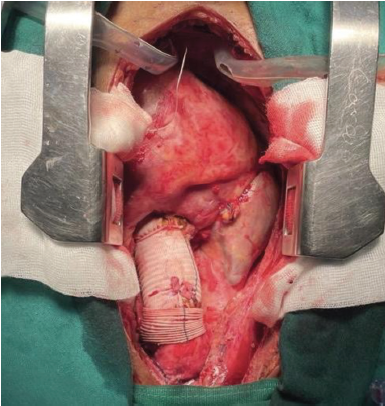

Después de la reimplantación de la válvula, es de suma importancia realizar una revisión de las valvas en busca de prolapso residual, simetría y la altura y profundidad de la coaptación. Esto es difícil de determinar mediante visualización directa al finalizar la reparación; afortunadamente, Schäfers et al. 16. introdujeron un calibrador para determinar la altura efectiva y verificar una adecuada coaptación de la válvula. Utilizamos este dispositivo en ambos pacientes y la medición se encontraba en el rango de efectividad (7-12 mm)17. (Figura 2)

Figura 2 Fotografía de campo quirúrgico. Medición de la altura efectiva utilizando el calibrador de Schäfers.